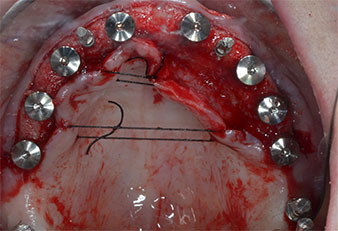

Debido al hueso relativamente duro (D2) existente en el sector anterior, los sitios de los implantes largos de 10 mm de las posiciones 11 y 21 se finalizaron con una fresa rotatoria de 4 mm de diámetro, en combinación con un contra-ángulo quirúrgico WS-75 L de W&H, el motor de implantes Implantmed de W&H y el módulo opcional Osstell ISQ de W&H. En cambio, debido a la existencia de hueso blando, los sitios posteriores se prepararon hasta un diámetro final de 3 mm utilizando el inserto Piezomed I3P. Por último, los implantes se colocaron a nivel crestal para su osteointegración durante tres meses (figuras 6-10). La prótesis existente se mantuvo sobre cuatro implantes provisionales (figura 8).